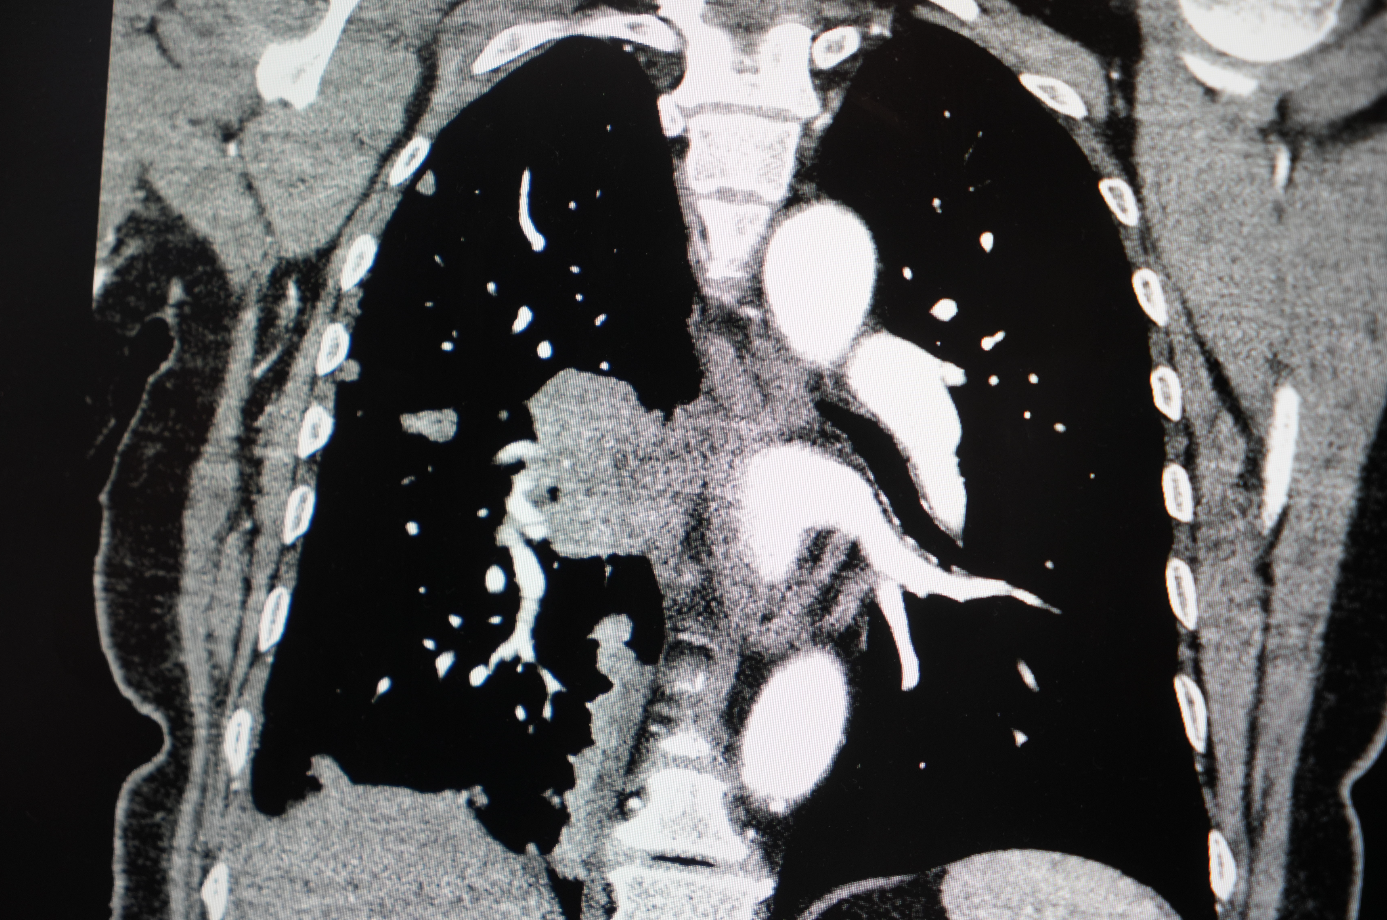

Akciğer kanseri vakalarındaki artışı da vurgulayan Özkaya, "Son yıllarda hem sigara içen hem de hiç sigara kullanmamış bireylerde akciğer kanseri vakalarında dikkat çekici bir artış görüyoruz. Özellikle kadınlarda adenokarsinom tipi akciğer kanseri belirgin şekilde artış göstermektedir., Yapılan son araştırmalara göre akciğer kanseri teşhislerinin yaklaşık yüzde 20'si hiç sigara içmemiş bireylerde konuluyor. Bunun en önemli nedeni pasif içiciliktir. Yani siz sigara içmeseniz bile, yakın çevrenizde sigara içiliyorsa akciğer kanseri riskiyle karşı karşıya kalabilirsiniz" diye konuştu.